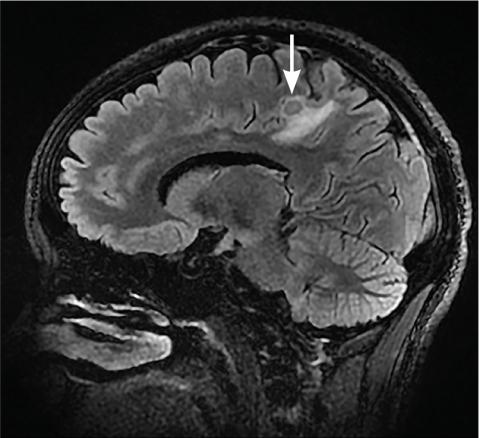

L’imagerie montrait : sur la tomodensitométrie (TDM) thoracique une miliaire tuberculeuse pulmonaire et des adénopathies médiastinales ; sur l’imagerie par résonance magnétique (IRM) du rachis une spondylodiscite T11-T12 (fig. 1 ) ; sur la TDM abdominale des abcès paravertébraux de T9 à T12 le long des psoas (fig. 2 , flèches blanches) et des lésions micronodulaires hépatiques multiples (fig. 2 , flèche jaune) ; sur l’IRM myocardique des signes de péricardite (fig. 3 , flèches). La ponction lombaire montrait une méningite. Un tuberculome était visible sur l’IRM cérébrale, entouré d’un œdème périlésionnel (fig. 4 ). Le diagnostic de tuberculose disséminée était prouvé par polymerase chain reaction sur une ponction d’abcès. Compte tenu de l’atteinte neuroméningée, un traitement adjuvant par corticothérapie s’imposait dans le cas présent, de même qu’une antibiothérapie de 9 à 12 mois.1